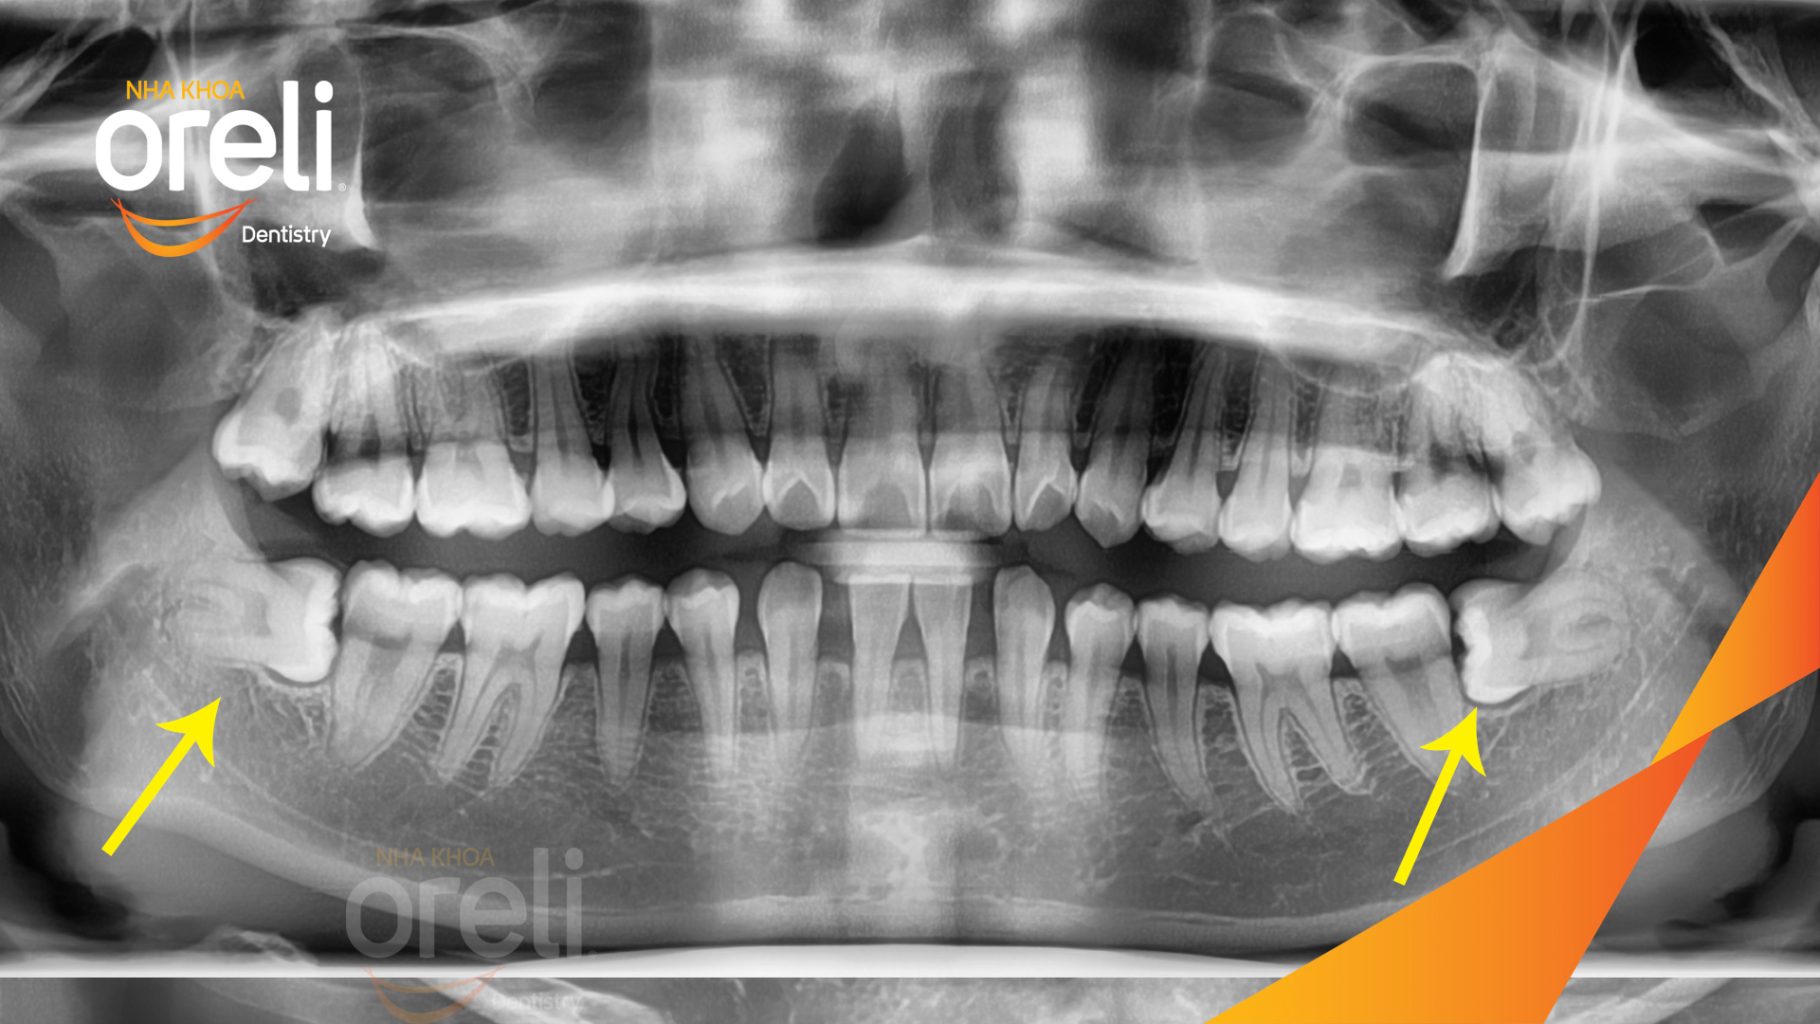

Nhổ răng khôn hàm dưới mọc lệch – Ca thực tế tại Oreli Buôn Ma Thuột

Tình trạng: Răng khôn hàm dưới mọc lệch ngang 90 độ

Giải pháp: Nhổ răng khôn hàm dưới bên trái

Kết quả: Toàn bộ răng 8 hàm dưới bên trái được lấy bỏ

Hình ảnh thực tế